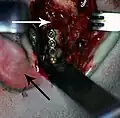

Open reduction with direct skeletal fixation allows the bones to be directly mandibulated through an incision so that the fractured ends meet, then they can be secured together either rigidly (with screws or plates and screws) or non-rigidly (with transosseous wires). There are a multitude of various plate and screw combinations including compression plates, non-compression plates, lag-screws, mini-plates and biodegradable plates.

Rigid internal fixation of parasymphysis fracture of the mandible. White arrow marks fracture, black arrow marks arch bar on lower teeth

Rigid internal fixation of parasymphysis fracture of the mandible. White arrow marks fracture, black arrow marks arch bar on lower teeth -